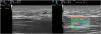

A 32-year-old woman presented with induration of the arms and the external aspect of the knees that had begun 3 months earlier and limited her movement (Fig. 1). Skin ultrasound (18-MHz linear probe, MyLab Class C, Esaote) revealed thickening of the muscular fascia, alterations of the echostructure of the superficial hypodermis, and a dermis with no pathological findings (Fig. 2A). Elastography showed increased stiffness of the muscle fascia (Fig. 2B). Based on these findings eosinophilic fasciitis (EF) was suspected, and was subsequently confirmed by nuclear magnetic resonance imaging and fascia biopsy. EF is a rare fibrosing disorder that manifests as pseudocellulitis (peau d’orange appearance), together with groove sign. Definitive diagnosis requires biopsy, which should include both the hypodermis and muscle fascia. Few articles have evaluated the diagnostic utility of ultrasound in EF. Ultrasound reveals an increase in the thickness of the muscular fascia, accompanied or not by alterations in the hypodermis. Elastography is a technique based on the detection of changes in tissue elasticity using ultrasound. Cutaneous ultrasound with elastography proved useful in guiding the diagnosis of this case of EF, and could potentially be used in follow-up to monitor treatment response.